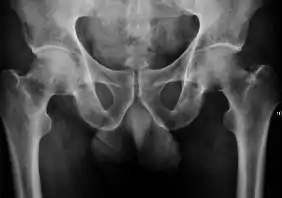

Projectional radiography ("X-ray") is the first imaging technique of choice in hip pain, not only in older people with suspected osteoarthritis but also in young people without any such suspicion. In this case plain radiography allows categorization as normal hip or dysplastic hip, or with impingement signs, pincer, cam, or a combination of both.[1]

Projectional radiography ("X-ray") is currently useful not only in older people in whom osteoarthritis of the hip is suspected but also in younger people without osteoarthritis, who are being evaluated for femoroacetabular impingement (FAI) or hip dysplasia.[1]

Plain radiography allows us to categorize the hip as normal or dysplastic or with impingement signs (pincer, cam, or a combination of both). Besides these, pathologic processes like osteoarthritis, inflammatory diseases, infection, or tumors can also be identified (Figure 1).[1]

Figure 1.

Radiography in normal hip

X-ray in pincer impingement type of hip dysplasia

X-ray of cam

Hip in osteoarthritis

Septic arthritis

X-ray in pediatrics